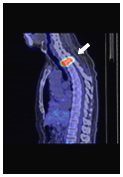

身体の形態も

病変も一目瞭然

病変は見えているが

身体の形態はぼやけている

身体の形態ははっきり

見えているが病変が不明